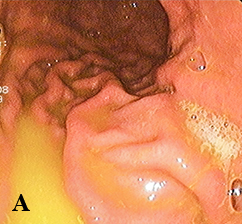

Диагностика ДГР при ЭГДС легко устанавливается по наличию желтого, зеленого окрашивания содержимого желудка, т. е. по наличию желчи в желудочном соке. Желтое содержимое желудка соответствует легкой степени (см. рис. 1а); прозрачное светло-зеленое — средней степени (см. рис. 1б) и мутное темно-зеленое — тяжелой степени рефлюкса (см. рис. 1в). ЭГДС не может провоцировать ДГР, так как интубация пищевода и прохождение эндоскопа по пищеводу занимает несколько секунд. Факт поступления желчи из привратника не является физиологическим и не может быть классифицирован как истинный ДГР.

Рис. 1. Степени тяжести ДГР при ЭГДС.